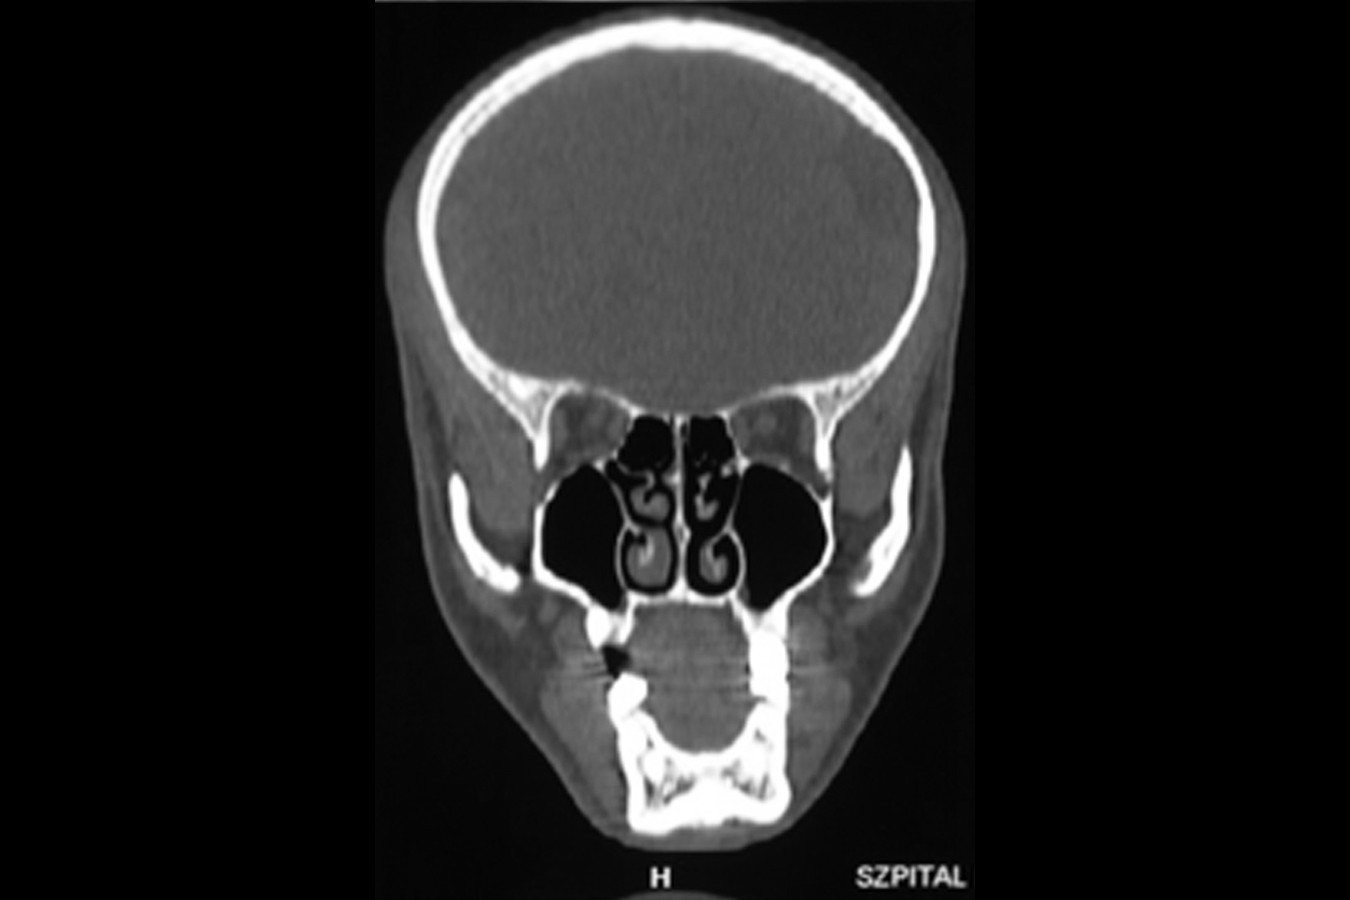

Przed podjęciem leczenia należy określić stopień zaniku kości szczęk oraz żuchwy. W tym celu przeprowadza się badanie kliniczne oraz odpowiednią diagnostykę obrazową pacjenta. Uwzględnia ona zdjęcie panoramiczne OPG jako podstawę dwuwymiarowego obrazowania podłoża kostnego oraz możliwe jest badanie tomograficzne CT lub bardziej precyzyjna tomografia stożkowa CBCT. Opcjonalnie wykorzystywana diagnostycznie tomografia pozwala na bardziej wnikliwą ocenę stopnia zaniku kości w trójwymiarowym, przestrzennym obrazie.

ANATOMIA ZATOK SZCZĘKOWYCH:

Zatoki szczękowe to symetrycznie umieszczone w kościach szczęk przestrzenie powietrzne, posiadające komunikację z jamą nosa. Średnio pojemność zatok wynosi 24 cm3, a ściany wyścielone są błoną śluzową (membrana Schneidera). Dno zatoki szczękowej stanowi wyrostek zębodołowy, w którym umieszczone są zęby, często zlokalizowane tuż pod cienką wyściółką zatoki. Statystycznie najwęższy obszar kostny w tej strefie zlokalizowany jest na wysokości zębodołów pierwszego i drugiego zęba trzonowego.